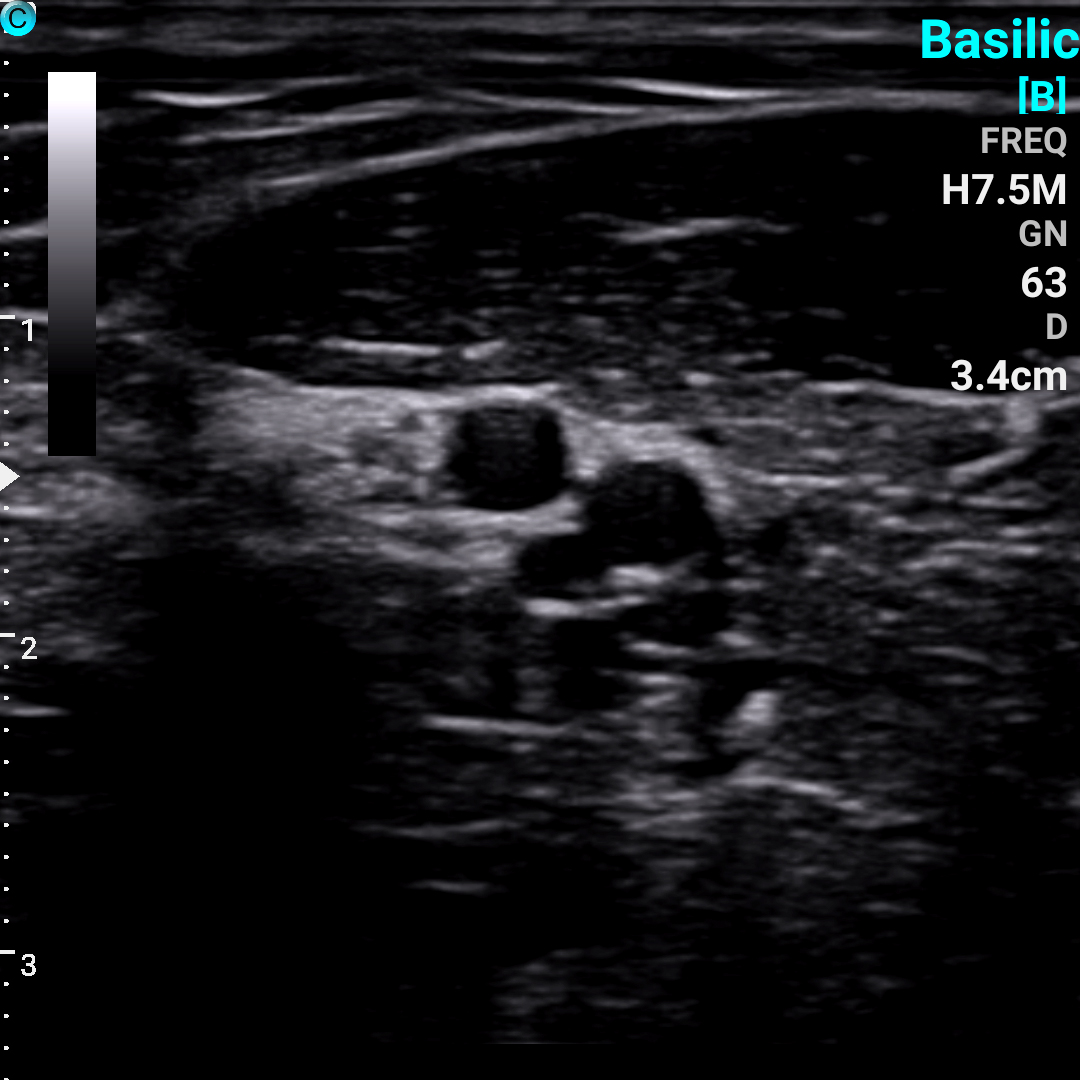

贵要静脉 B模式